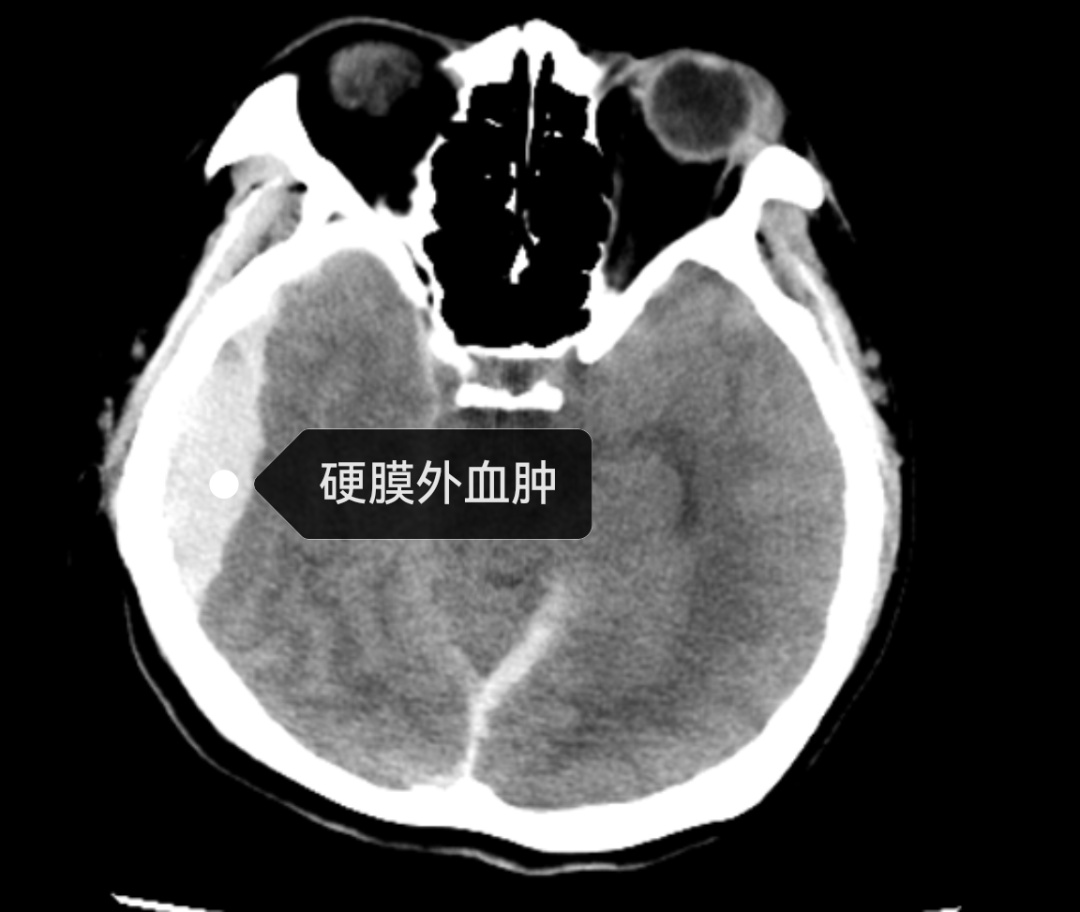

入院时,刘女士面部发红、眼结膜充血,口腔黏膜也有大小不等的出血点,更为严重的是,她的头部CT结果显示“硬膜下出血”。